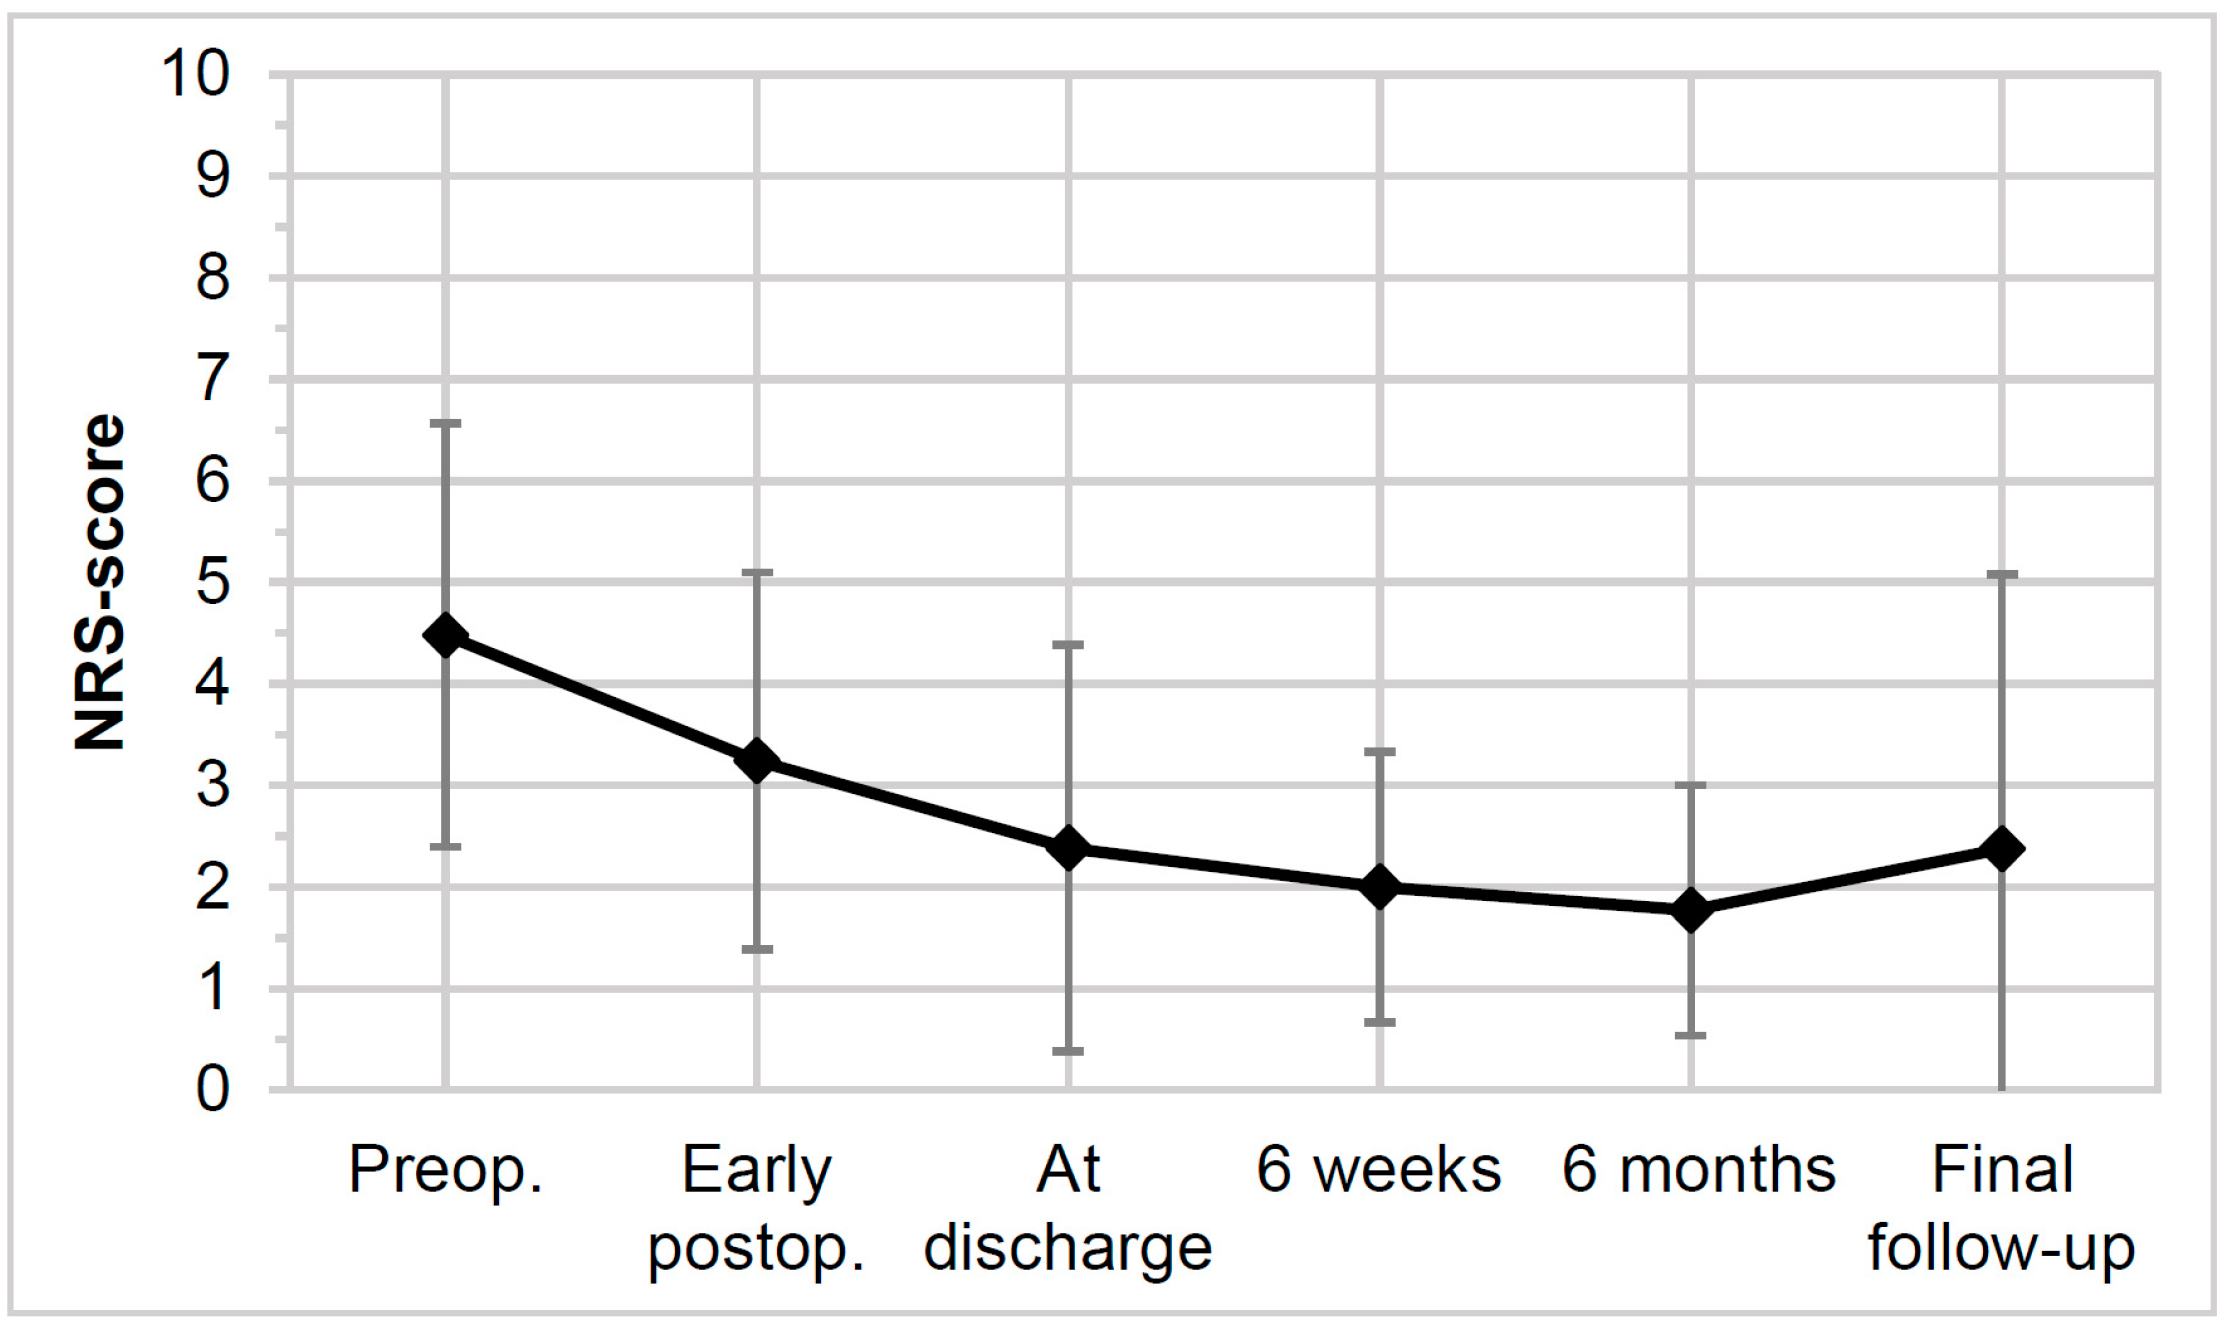

2.4. Clinical Outcome

3.3. Clinical Outcomes